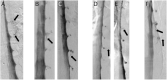

Results: Among 398 patients with SIH and extradural CSF on spinal imaging, multiplicity of CSF leaks was observed in none of 291 patients with type 1a ventral leaks and in 4 (6.2%) of 65 patients with type 1b (postero-) lateral leaks. Among 97 patients with SIH from spinal CSF-venous fistulas (type 3 leaks) who did not have extradural CSF on spinal imaging, 9 patients (9.3%) had multiple fistulas (p < 0.0001 for comparison between groups). Type 3 and type 1a or 1b CSF leaks coexisted in an additional 5 patients.

Conclusions: Among patients with SIH, multiplicity of CSF leaks was observed radiographically in none of the patients with ventral leaks, in 6% of patients with lateral leaks, and in 9% of patients with CSF-venous fistulas. These results suggest that patients with SIH can be reassured that the occurrence of multiple CSF leaks is negligible to uncommon at most, depending on the type of CSF leak.